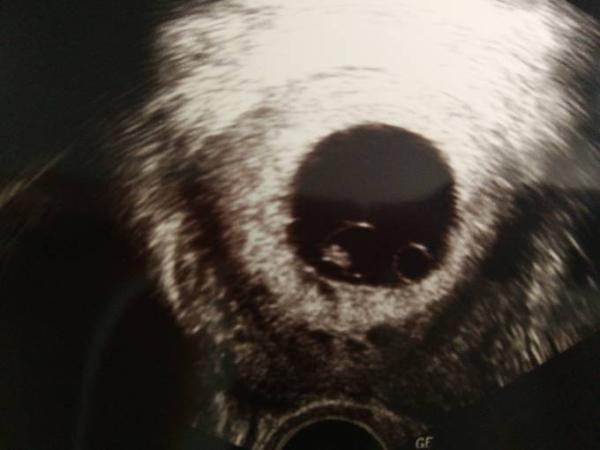

Guten Morgen ihr Lieben. Gleich ist es soweit ich habe heute mittag meine 2.uss ich bin laut rechnen bei 7+4 und hoffe man kann das herzchen sehen und ich bekomme hoffentlich meinen mutterpass. Ich bin so aufgeregt

Man sieht keinen Herzschlag

Ich müsste in der 8.ssw sein. Der embrio ist auch dem entsprechend entwickelt aber es schlägt kein Herz. Ich soll morgen ins Krankenhaus und die entscheiden dann wies weiter geht